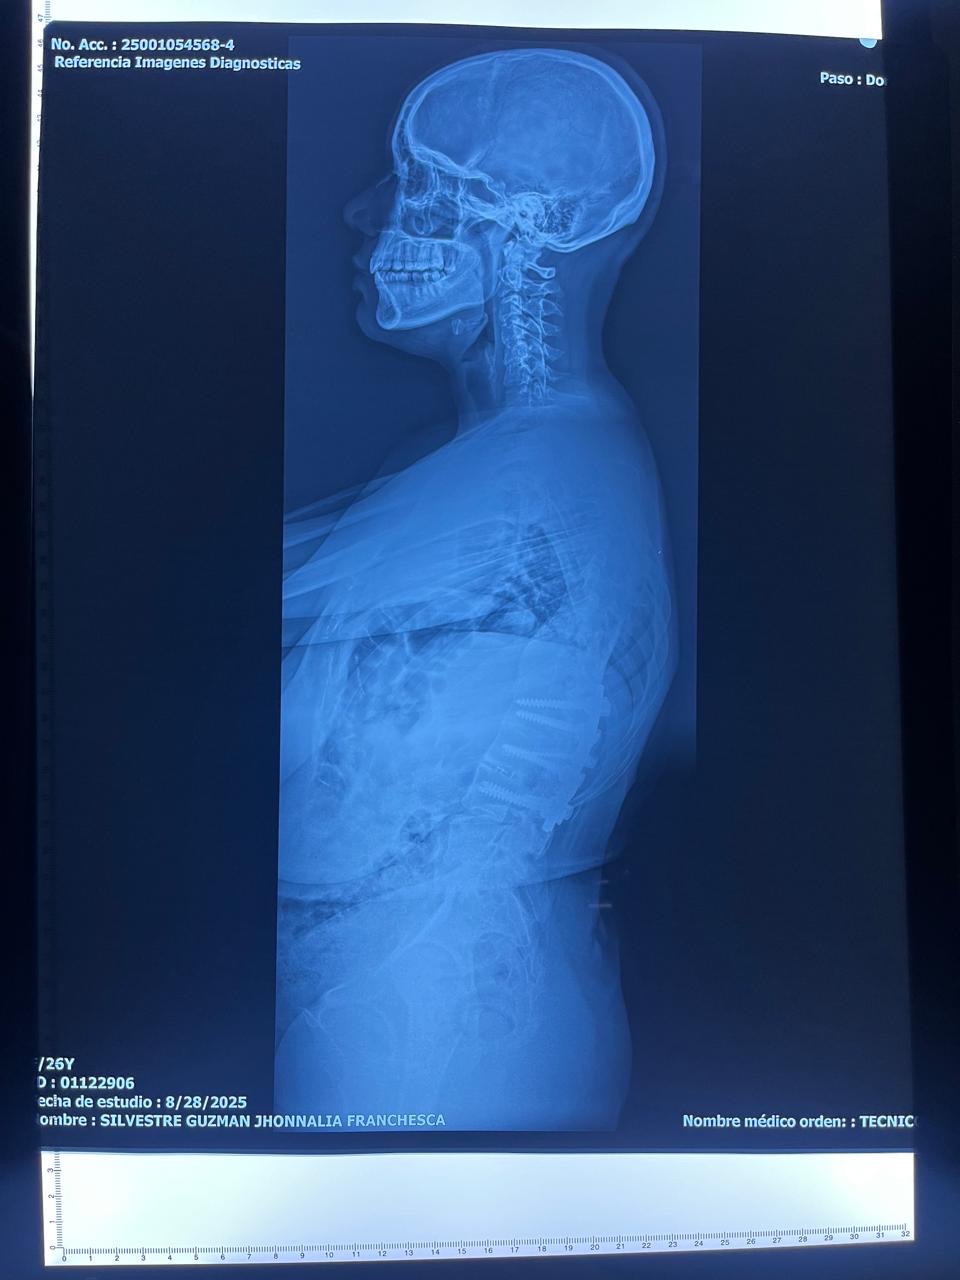

Quiero contarte un poco sobre mi historia: desde la adolescencia, vivo con una condición llamada escoliosis dorso-lumbar, en la cual la columna se curva de manera anormal formando una S. En mi caso, la curva superior se dobla hacia el lado derecho y la inferior hacia el lado izquierdo. Esto no solo afecta la forma de mi columna, sino que también comprime órganos vitales, provocando dolor constante y dificultades en mi respiración.

Desde los 11 años he pasado por 5 cirugías de alto riesgo intentando mejorar mi calidad de vida, pero la enfermedad ha seguido avanzando. Actualmente, aunque tengo 25 años, mis pulmones presentan un desgaste propio de más de 40 años debido a la compresión de mi columna. Mi cuerpo está físicamente afectado, vivo con dolor crónico diario, y cada día se hace más difícil realizar actividades normales.

Hoy necesito una nueva cirugía de columna que me permita recuperar movilidad, mejorar mi respiración y, sobre todo, vivir con menos dolor y mayor calidad de vida. Sin embargo, el costo de esta cirugía y de todo el proceso de recuperación es muy alto y por eso recurro a tu solidaridad.